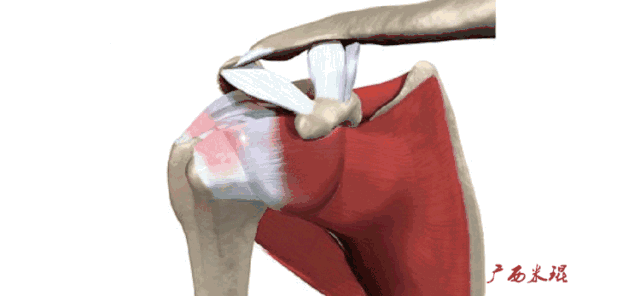

肩袖(Rotator cuff)损伤由Smith于1834年发现并命名,指组成肩袖的冈上肌、冈下肌、肩胛下肌和小圆肌的损伤。肩袖是以上4条肌腱共同组成的功能复合体,呈一个袖套状包绕肱骨头,维持盂肱关节的稳定,同时提供肩关节活动时所需的动力。

冈上肌和冈下肌在肱骨大结节上有共同止点,冈上肌和肩胛下肌在结节间沟处共同包绕肱二头肌长头腱。这样紧密的关系预示着肩袖的某一部分组织发生病变一般都会波及其余的肩袖组织,也是我们MRI阅片中必须要注意的。